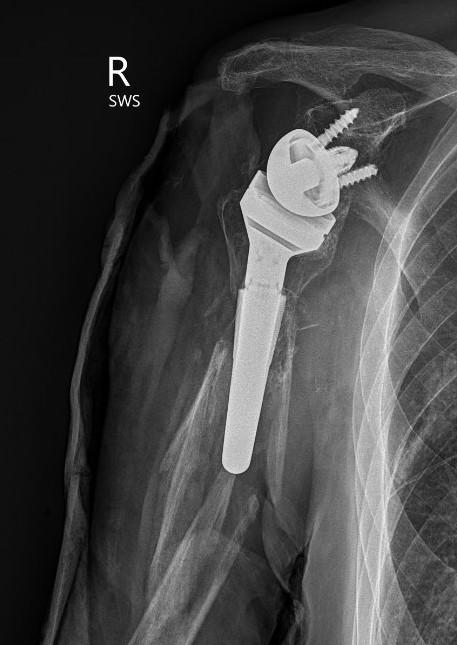

Periprosthetic fracture

Humeral shaft fractures

Hum shafthum shaftHum shaft

Stable humeral component treated with ORIF

hum #Hum #Hum #

Unstable humeral component